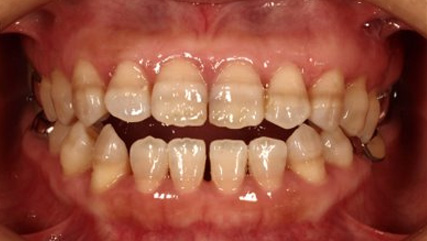

治療前

治療終了前